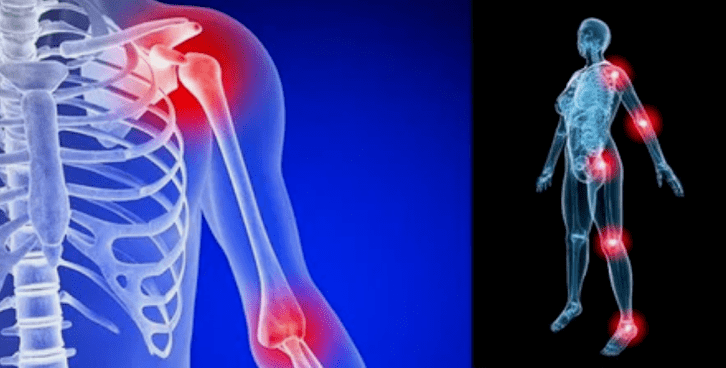

Gaixotasunaren adierazpenak lokalizazioaren arabera ez dira gutxi, sarritan seinaleak belaunetan, sorbaldan eta hip junturetan islatzen dira, karga altua dela eta.

- gorritasunarekin hantura. Gaixoaren artikulazioaren ondoan kokatzen da, horrek hanturazko prozesua eta gaixotasunaren progresioa adierazten ditu. Medikuak ulertzen du shell sinovialak kaltetuta daudela, horrek fluidoen metaketa eta mina areagotzea eragiten du;